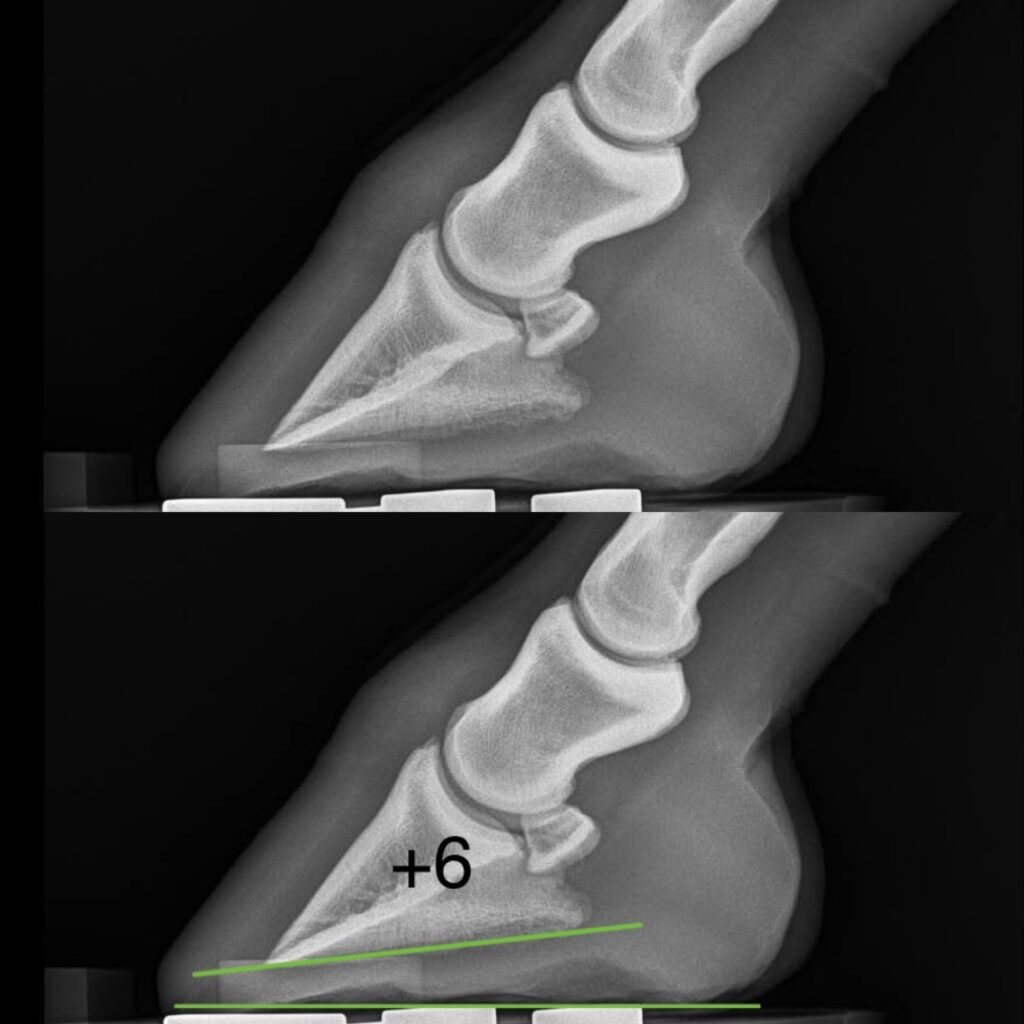

Hier rechts en onder zie je röntgenfoto’s met verschillende hoeken. De onderste groene lijn is de grondlijn, de bovenste groene lijn is de onderkant van het hoefbeentje. De graden staan erbij aangegeven. Kijk maar hoe anders de gewrichten op elkaar gestapeld staan bij de verschillende hoeken!